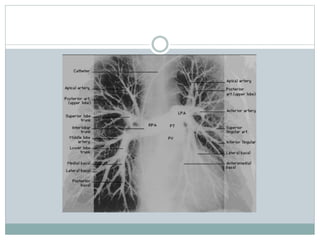

CT Anatomy

These two CT images show a large pulmonary embolus in the left main

branch of the pulmonary artery. On the left is a lateral view of the artery and

on the right is the anterior view of the same artery.